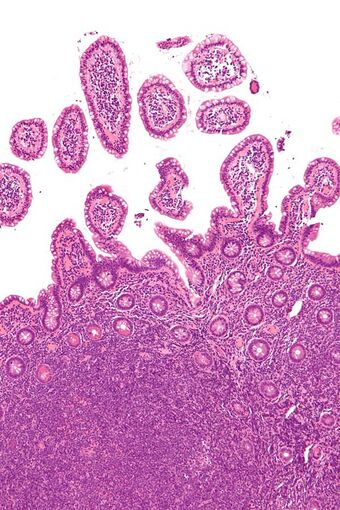

| Micrograph of mantle cell lymphoma, a type of non-Hodgkin lymphoma. Terminal ileum. H&E stain. |